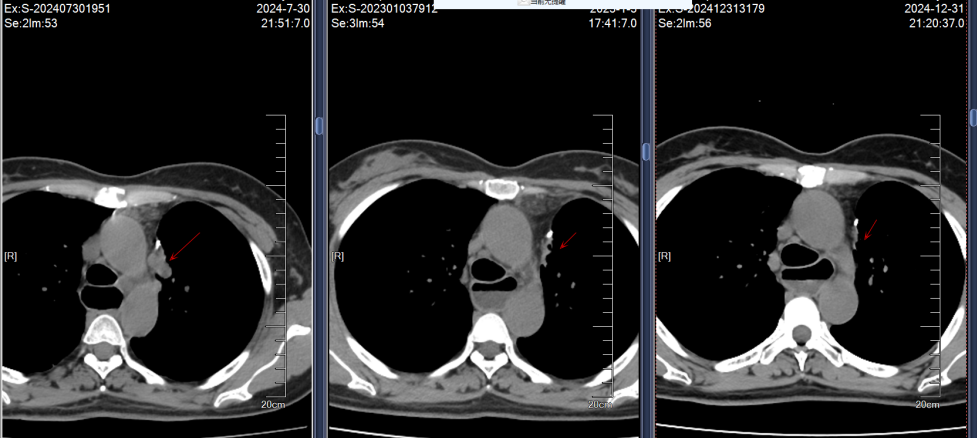

2024年7月30日胸部CT示:左上肺术区新增结节,两肺多发实性结节较前增多,肝S7新增结节;7月31日头颅MRI示左侧顶叶、小脑半球新增转移灶。结合影像及病史,确诊为ALK阳性晚期NSCLC复发伴多发转移(图1)。

影像学随访显示肺部、肝部的病灶完全消失,脑部的病灶缩小稳定;